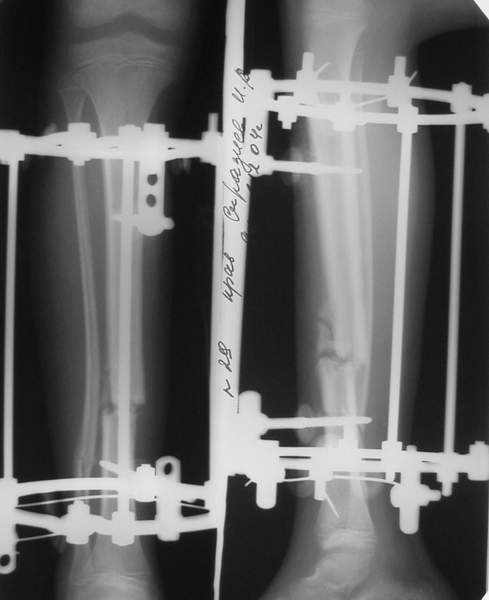

Под рукой прилагаемый пример. Как видите, "стриптиз-аппарат" (шутка проф. З.К.Башурова): 3 кольца-2 кольца-2 полукольца. В случае, который представил Евгений, характер повреждения позволил бы сразу использовать аппарат на основе 2 колец; в крайнем случае прокс. опора м.б. демонтирована сразу после репозиции.

В аттачтах №№ 1 и 2 - примеры, когда 2 кольца не позволили послеоперационно

исправить смещение фрагментов большеберцовой (по ширине и вальгусное).

А казалось бы (#2) - поиграй на штангах и все влетит.

1

1a